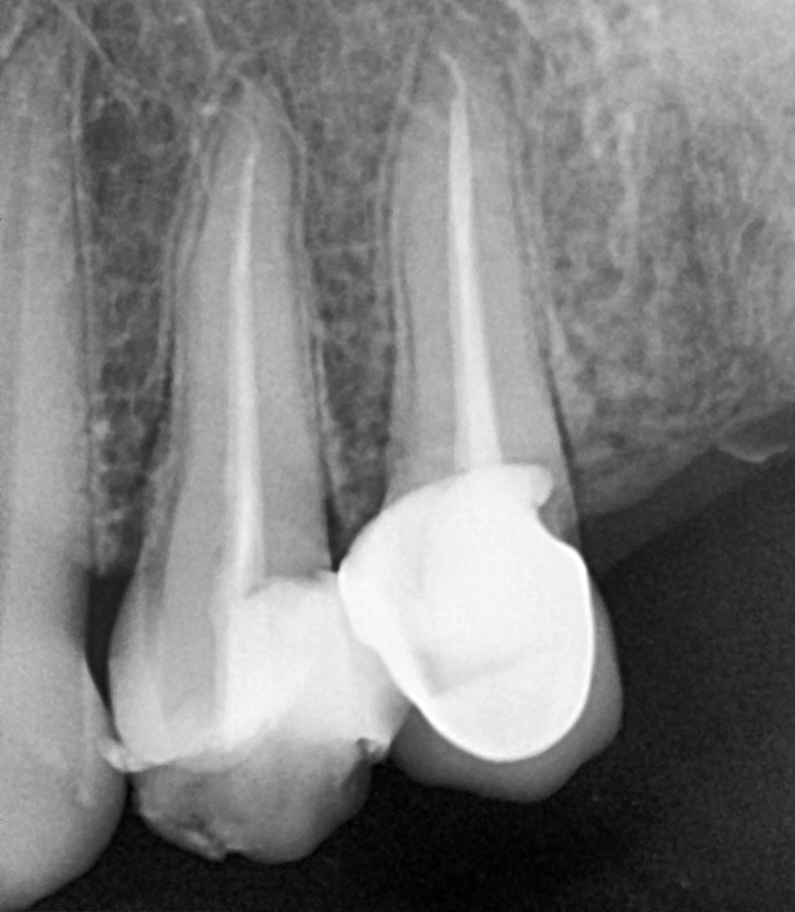

• Irrigate the tooth with antibacterial solutions, dry the tooth, Gutta Percha (rubber points) should be placed into the root canals.

• Once the Gutta Percha is placed, a temporary filling on the tooth or a permanent filling on the tooth can be placed.

Is crown required?

Depending on the tooth, it is quite common to recommend placing a crown over the tooth within 3 months after root canal treatment, to provide maximum protection for the tooth in the long term.

The reason for this is because a tooth that has undergone nerve infection and pulp is removed thus tooth has become weak and brittle. A lot of biting forces fall on teeth when we eat and chew, so placing a crown on the tooth provides the tooth the necessary strength and durability.

Gallery